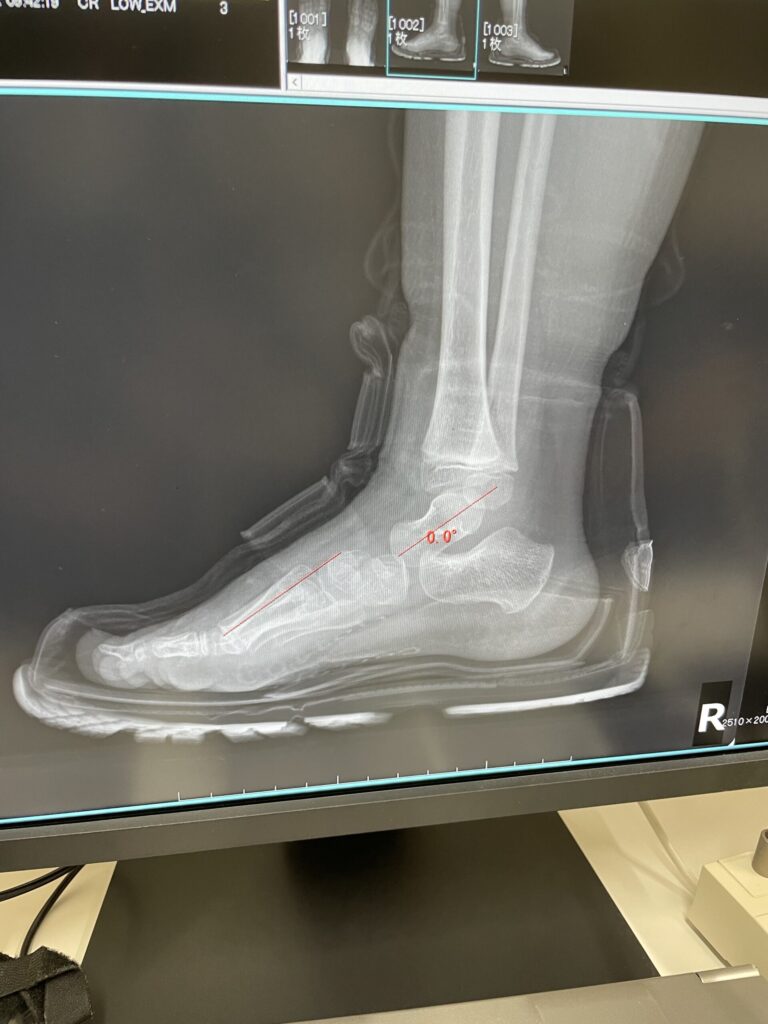

インソールの入った靴を履いた状態

インソールが完成し、整形外科で靴を履いた状態のレントゲンを撮影。

すると――

履いていない状態と、履いた状態では 全然違う

2枚目の写真。扁平足だった部分の骨が、しっかり持ち上がっていました。